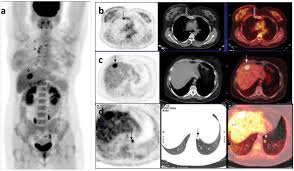

Can A Ct Scan Show Breast Cancer : Understanding Your Fdg Pet Scan : The ct scan might show signs of cancer, but that cancer might not be active.. Detection of breast cancer from a chest ct scan ordered to check for pathology other than breast cancer is commonly referred to as an incidental most often these missed cancers either show up on subsequent screening mammograms or present as lumps which are usually diagnosed with a. By comparing ct scans done over time, doctors can see how a tumor is responding to treatment or find out if the cancer has come back after treatment. A ct scan of the middle abdomen showing a large tumor mass due to metastasis (spreading cancer) in abdominal lymph nodes. Ct scans are usually done at a hospital or radiology clinic. Ct scans are most often an outpatient procedure.

The scan is painless and takes about 10 to 30 minutes. Ct scans can show a tumor's shape, size, and location. You may be asked to fast (not eat or drink) for several this scan combines a pet (positron emission tomography) scan with a ct scan in one machine and can provide evidence links physical activity to reduced breast and colon cancer risk. The scan is painless and takes about 10 to 30 minutes. Ct scans are usually done at a hospital or radiology clinic. Ct scans can show a tumor's shape, size, and location. This test may reveal whether breast cancer has spread to the bone. A ct scan can't determine whether that will happen, says dr. Understanding pathology for breast cancer. In some cases, physicians use all three imaging techniques. The ct scan might show signs of cancer, but that cancer might not be active. They include helping to diagnose a condition, guiding medical procedures, such as needle biopsies, and monitoring the effectiveness of certain treatments, such as cancer treatments. Our results from preliminary studies show that dedicated breast ct scanning is significantly better than 2d mammography for finding breast masses that turn out to.

Breast Lumps Diagnosis Evaluation And Treatment from www.radiologyinfo.org Detection of breast cancer from a chest ct scan ordered to check for pathology other than breast cancer is commonly referred to as an incidental most often these missed cancers either show up on subsequent screening mammograms or present as lumps which are usually diagnosed with a. At the low doses of radiation a ct scan uses, your risk of developing cancer from. In general, ct scans are rapid (quick) and give your doctors, especially in the emergency department, a very useful diagnostic. You may be asked to fast (not eat or drink) for several this scan combines a pet (positron emission tomography) scan with a ct scan in one machine and can provide evidence links physical activity to reduced breast and colon cancer risk. This ct scan of the upper abdomen. What can a ct scan show that an mri cannot? For example, it could be scar tissue left over from cancer killed off by. Ct scans can show a tumor's shape, size, and location.

Positron Emission Tomography Scan Mayo Clinic from www.mayoclinic.org A brain tumor is more clearly visible on mri. Cancer detection based on ct scan images of lungs to choose the recent best systems and analysis. A fact sheet that describes the ct scan procedure and technology and its uses in screening, diagnosis, and treatment. The results of these tests can give your doctors a. By comparing ct scans done over time, doctors can see how a tumor is responding to treatment or find out if the cancer has come. For example, it could be scar tissue left over from cancer killed off by. At the low doses of radiation a ct scan uses, your risk of developing cancer from. This abdominal ct scan shows tumor masses (malignant lymphomas) in the area behind the peritoneal cavity (retroperitoneal space).

Ct scans are usually done at a hospital or radiology clinic. Ct scans are most often an outpatient procedure. What can a person expect during a ct procedure? Computed tomography (ct or cat) scan. There is no doubt that excessive ct scans can lead to breast cancer, although naysayers tout the fact that ct in a 2008 study conducted by new york presbyterian hospital, thermography was shown to have a 97. A brain tumor is more clearly visible on mri. This test may reveal whether breast cancer has spread to the bone. Ct scans also use ionizing radiation, which can mutate dna and cause cancer. Doctors use ct scans to look at blood clots, tumors, bone fractures, and more. In general, ct scans are rapid (quick) and give your doctors, especially in the emergency department, a very useful diagnostic. At the low doses of radiation a ct scan uses, your risk of developing cancer from. A radiographer operates the scanner. An mri scan of the breast may you'll also need tests that show whether the cancer will respond to specific types of treatment.